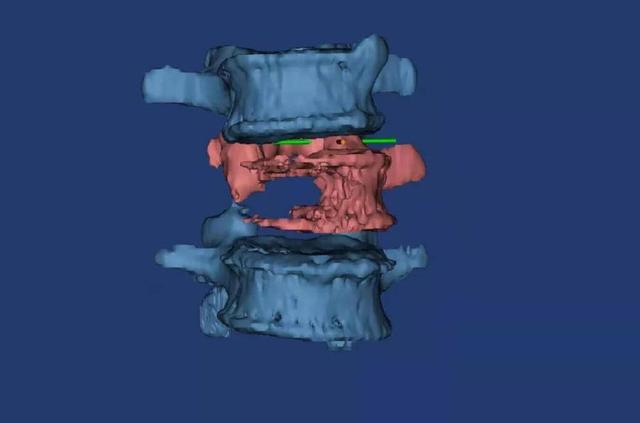

△术前3D打印模型显示腰3椎体右侧半被肿瘤“吃”空了。

△术前3D打印规划术中人工椎体大小形态。